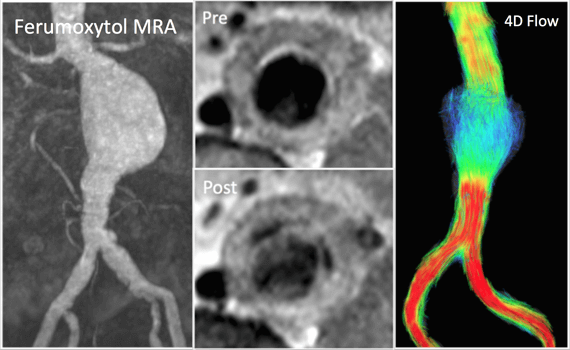

Goal: To elucidate the mechanisms of growth and rupture of small abdominal aortic aneurysms (AAAs) with a combined hemodynamic and inflammatory assessment using functional aortic imaging techniques.

Motivation: Abdominal aortic aneurysms (AAA) are common and can be life-threatening if they progress to rupture. They have been reported in 5% of older men and account for over 15,000 deaths per year. Basic vVessel dimensions are currently the primary imaging measurement clinically used clinically to risk-stratify patients. But there is more to the story than dimensions. Wall stress estimated with computational modeling may better predict growth and rupture than diameters. Growth is often not continuous, and instead marked by periods of rapid growth followed by quiescence. Small series report that unrelated surgical procedures can precipitate AAA rupture. These findings suggest that episodic and heterogeneous inflammatory processes in concert with adverse hemodynamics are important for the progression of AAA disease.

Rationale: The complexity of aortic disease is more fully revealed with new functional imaging techniques than with conventional anatomic analysis alone. While AAA has been extensively studied, the mechanisms of disease progression have not been fully elucidated. If better understood, the management of patients with small AAAs (< 5.5cm) could be significantly improved. Many of these aneurysms can be followed safely with a long screening interval of 2-3 years, but some may progress to rupture. Identifying this subset would greatly streamline the surveillance imaging of the millions of patients with AAA. On the other hand, the majority of AAAs never rupture, and identifying low risk patients could help better manage resources and subject only those patients at truly elevated risk to intervention.

We hypothesize that the systemic inflammation experienced with unrelated surgery will lead to AAA growth, and that this growth will occur at sites of unfavorable hemodynamics. Revealing such a combined inflammatory and hemodynamic mechanism for progression of AAA disease would constitute a substantial advancement in knowledge that would have both direct and broad clinical implications.

Strategy: Aortic wall inflammation can be evaluated with the MRI contrast agent ferumoxytol, which has macrophage-selective properties on delayed imaging. MRI also offers a unique and comprehensive assessment of aortic hemodynamics. Blood flow imaging with 3D time-resolved, 3D phase- contrast MRI (4D Flow) allows quantification of key secondary vascular parameters including turbulence and wall shear stress (WSS). Cine Displacement Encoding with Stimulated Echos (DENSE) can quantify regional stretch differences experienced by the vessel wall. Computational modeling based on MRI volumetric data can be used to calculate wall stress. We propose that analysis of these hemodynamic parameters along with transient inflammation will be central to understanding the progression of AAA disease., we have found an excellent and clinically relevant disease process for demonstrating the potential of 4D Flow in the management of patients with cardiovascular disease.

We intend to study patients with small AAAs before and after unrelated surgery with a combined inflammatory and hemodynamic assessment, and follow their progress with regular surveillance imaging.

Expected Outcome and Impact: The goal of our study is to uncover important inflammatory changes and adverse hemodynamics that are not addressed with current imaging, and use them to predict disease progression. Our approach is unique both in our targeting of patients undergoing unrelated surgery and our comprehensive use of new functional imaging techniques. We seek to meaningfully advance the assessment of risk in patients who do not meet current intervention thresholds and improve outcomes by refining surveillance imaging regimens and decisions regarding early intervention for AAAs.